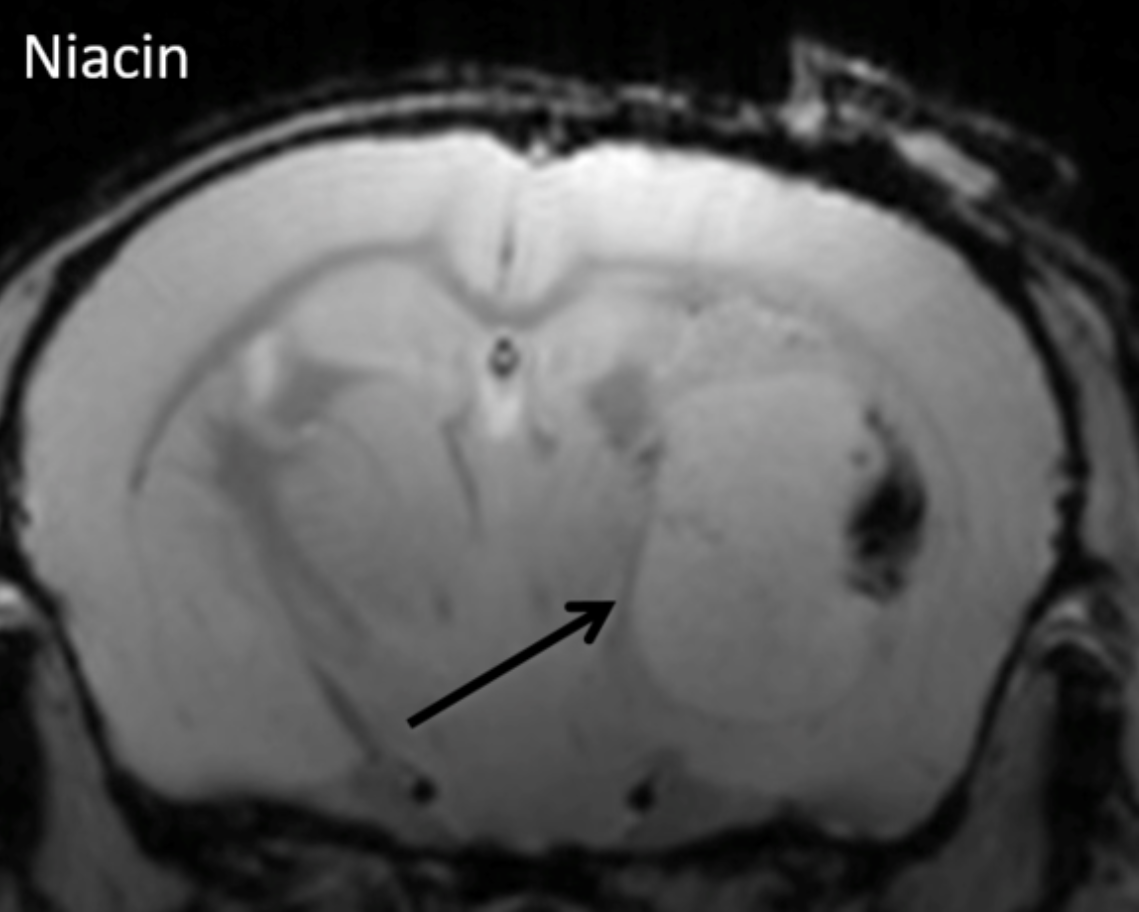

niacin.png

MRI shows that the huge growth capacity of glioblastoma tumour mass (arrow) within the brain in an experimental model was attenuated by niacin therapy compared to control.

Images from the Yong lab